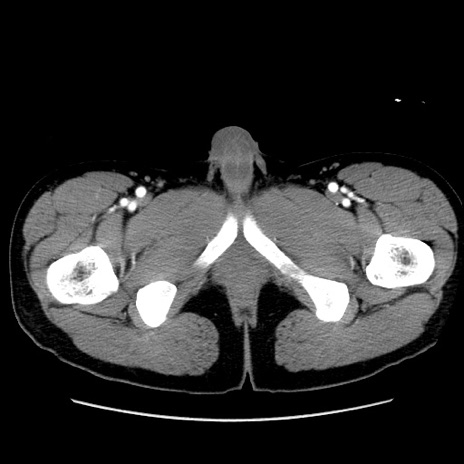

冠状断像

【症例】20歳代 男性

【主訴】心窩部痛

【現病歴】今朝より上腹部痛あり。一旦軽快していたが再度出現したため救急要請。昨日夕に白身の魚を含む刺身を食べた。

【身体所見】BP 136/89mmHg、HR 74/min、BT 37.0℃、腹部:膨満、軟、心窩部に圧痛あり。反跳痛なし、筋性防御なし、腸雑音やや亢進あり。

【データ】WBC 17700、CRP 0.48